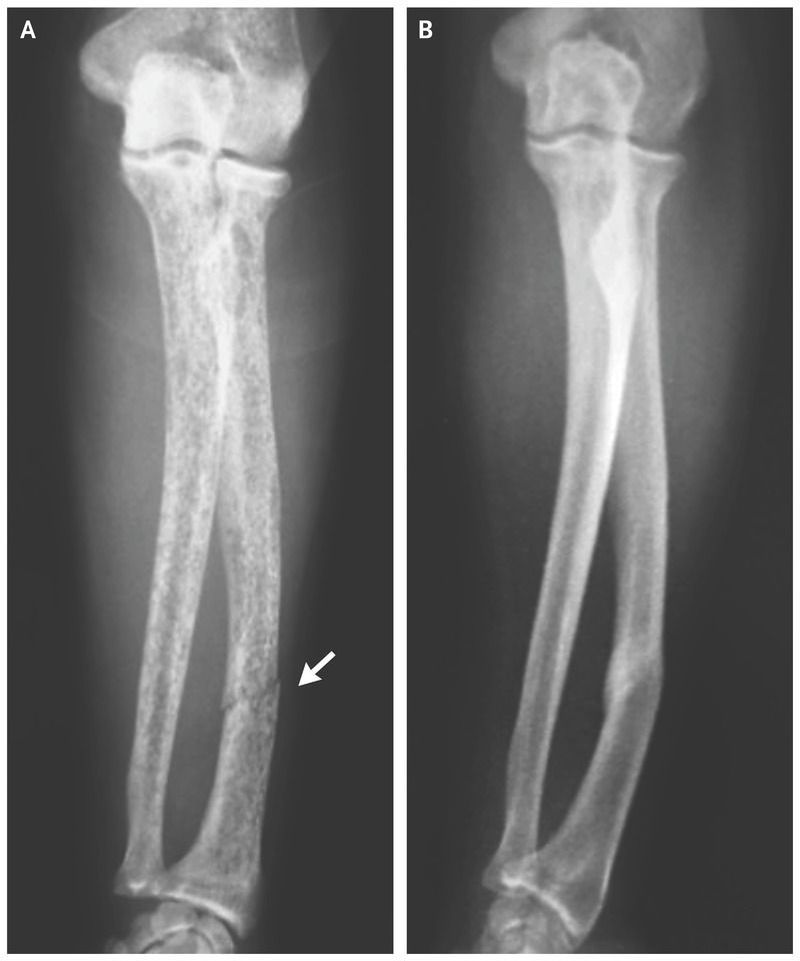

A 45-year-old man presented to the orthopedic clinic with pain in his left forearm that he had first felt while gripping a railing 1 day earlier. A plain radiograph of the left arm showed a diaphyseal radial fracture (Panel A, arrow) and a diffusely low-density, mottled appearance of the radius and ulna. Two months before presentation, the patient had received a diagnosis of primary hyperparathyroidism, with an intact parathyroid hormone level of 3590 pg per milliliter (reference range, 10 to 65) and a serum calcium level of 13.0 mg per deciliter (3.25 mmol per liter; reference range, 8.5 to 10.2 mg per deciliter [2.12 to 2.55 mmol per liter]). He underwent parathyroidectomy and was found to have parathyroid carcinoma, which is a rare cause of primary hyperparathyroidism and can manifest as markedly elevated parathyroid hormone levels. Evaluation at the time of diagnosis showed no evidence of metastatic disease. The patient’s forearm was placed in a splint for 6 weeks, and he received vitamin D and calcium supplementation. A plain radiograph obtained 1 year after the diagnosis of the fracture showed union of the radial fracture and normal-appearing bone density (Panel B). One year after the parathyroidectomy, the patient’s parathyroid hormone level was 48 pg per milliliter and his calcium level was 9.0 mg per deciliter (2.25 mmol per liter).